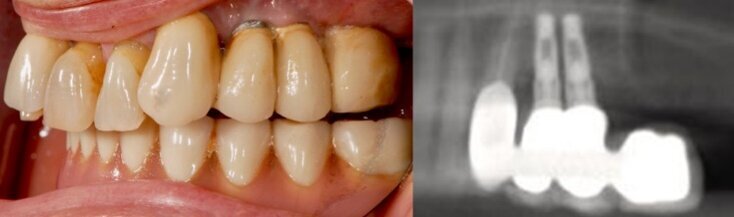

Fig. 8 - Radiografie endorali di controllo a 6 mesi dal posizionamento implantare. Si osserva un eccellente mantenimento dei livelli dei tessuti ossei peri-implantari.

Fig. 1 - Aspetto clinico e radiografico della paziente alla presentazione. Gli impianti in posizione 2.4 e 2.5 presentano un sondaggio > 5 mm; si noti come in corrispondenza dei due impianti ci fosse gemizio purulento peri-implantare spontaneo.

La paziente, di 64 anni, sana e non fumatrice, veniva riferita per un ascesso in corrispondenza di un ponte cementato su pilastro naturale e su impianti, da 2.3 a 2.5 con un elemento in estensione (Fig. 1). L’esame clinico e radiografico mostrava una perimplantite non trattabile a carico di entrambi gli impianti, una grave atrofia ossea e un mucocele asintomatico nel seno omolaterale. Rimossi gli impianti (Fig. 2), la paziente acconsentiva all’esecuzione di un rialzo di seno e una concomitante rigenerazione ossea verticale, e l’inserimento differito di quattro impianti da caricare possibilmente per via immediata. Non si è prevista l’asportazione del mucocele, essendo questo di modeste dimensioni e asintomatico. In posizione 2.4 lo spessore crestale era di 8,5 mm e la distanza cresta ossea/pavimento cavità nasale di 4,4 mm. In posizione 2.6 l’altezza della cresta ossea residua era inferiore ad 1 mm (Fig. 3).